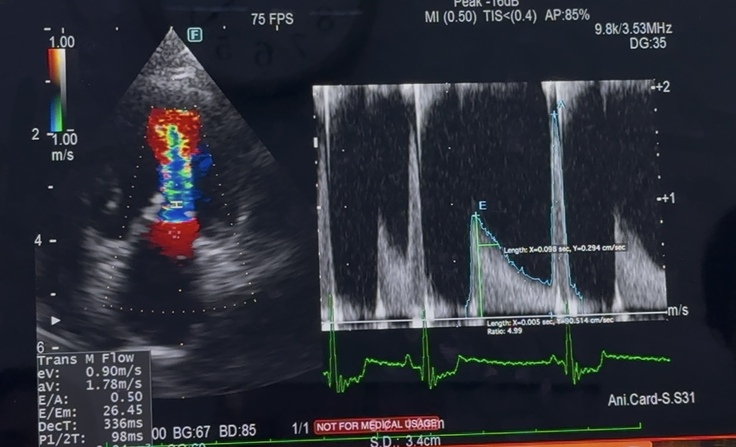

心臓の手術した側の心排出量に

低下がみられ

その原因に多い、肺高血圧症も

やや悪化している様…との事…